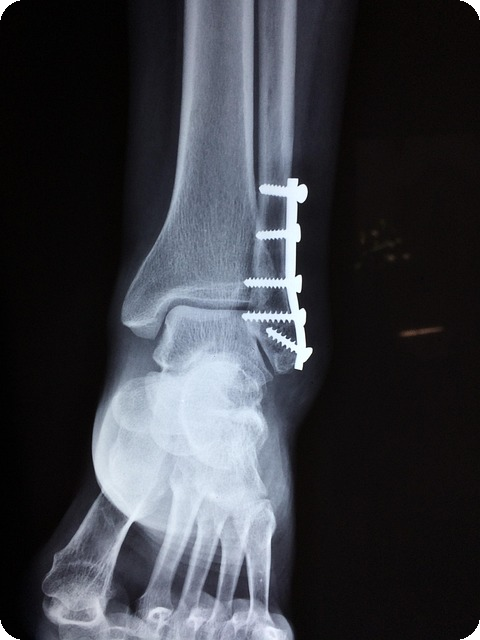

골다공증은 뼈의 질과 양이 감소하여 뼈가 약해지는 상태를 말합니다. 이 질환은 특히 50세 이상의 여성에게 많은 영향을 미치며, 골절 위험을 높입니다. 골다공증으로 인한 골절은 종종 심각한 건강 문제로 이어질 수 있으며, 회복 과정에서도 많은 시간이 필요하므로, 이를 예방하는 것이 가장 중요합니다.

골다공증은 뼈의 밀도와 강도가 감소하여 골절 위험이 높아지는 질환입니다. 특히 중년 이상에서 증가하는 경향이 있어 조기 예방이 중요합니다. 다음은 골다공증 예방을 위한 실천 팁입니다.